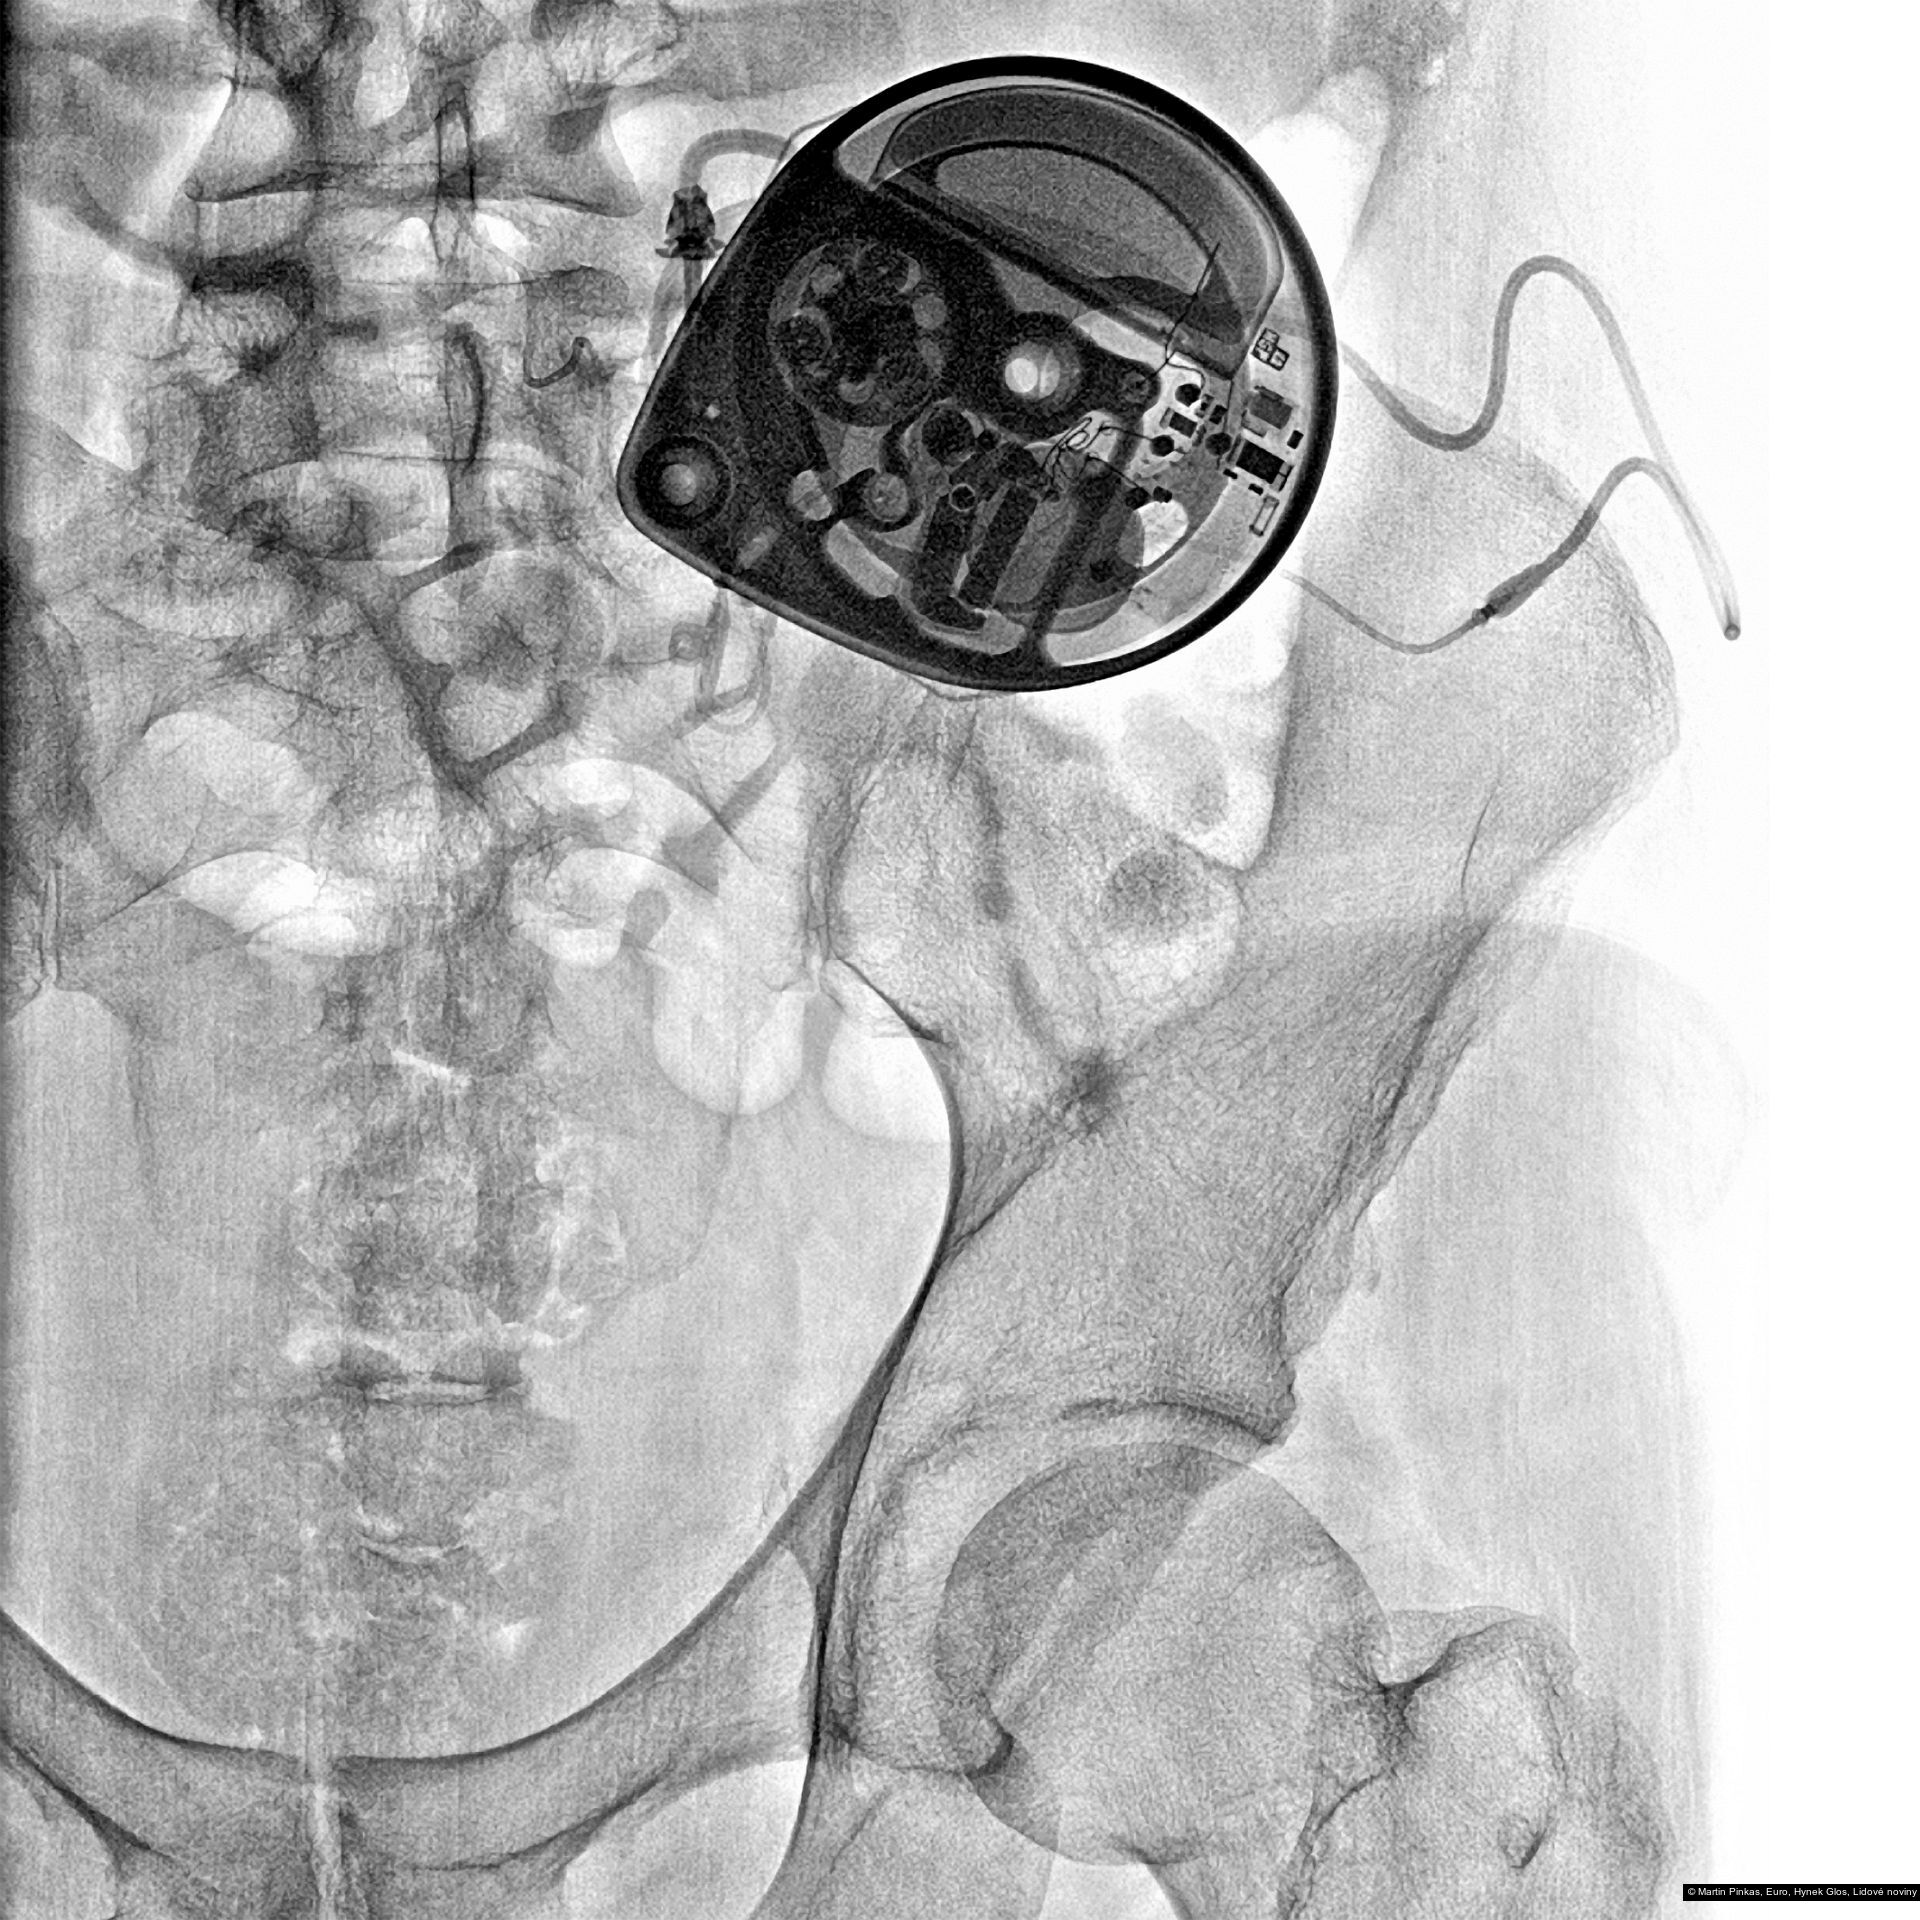

Příspěvek: X-portrait, nelékařské rentgenové portréty handicapovaných sportovců, Praha, Mostiště, 6.8. - 15.9.2010

Autor: Hynek Glos, Martin Pinkas

Příspěvek: X-portrait, nelékařské rentgenové portréty handicapovaných sportovců, Praha, Mostiště, 6.8. - 15.9.2010

Autor: Hynek Glos, Martin Pinkas

Příspěvek: X-portrait, nelékařské rentgenové portréty handicapovaných sportovců, Praha, Mostiště, 6.8. - 15.9.2010

Autor: Hynek Glos, Martin Pinkas

Příspěvek: X-portrait, nelékařské rentgenové portréty handicapovaných sportovců, Praha, Mostiště, 6.8. - 15.9.2010

Autor: Hynek Glos, Martin Pinkas

Příspěvek: X-portrait, nelékařské rentgenové portréty handicapovaných sportovců, Praha, Mostiště, 6.8. - 15.9.2010

Autor: Hynek Glos, Martin Pinkas

Příspěvek: X-portrait, nelékařské rentgenové portréty handicapovaných sportovců, Praha, Mostiště, 6.8. - 15.9.2010

Autor: Hynek Glos, Martin Pinkas

Příspěvek: X-portrait, nelékařské rentgenové portréty handicapovaných sportovců, Praha, Mostiště, 6.8. - 15.9.2010

Autor: Hynek Glos, Martin Pinkas

Příspěvek: X-portrait, nelékařské rentgenové portréty handicapovaných sportovců, Praha, Mostiště, 6.8. - 15.9.2010

Autor: Hynek Glos, Martin Pinkas

Příspěvek: X-portrait, nelékařské rentgenové portréty handicapovaných sportovců, Praha, Mostiště, 6.8. - 15.9.2010

Autor: Hynek Glos, Martin Pinkas